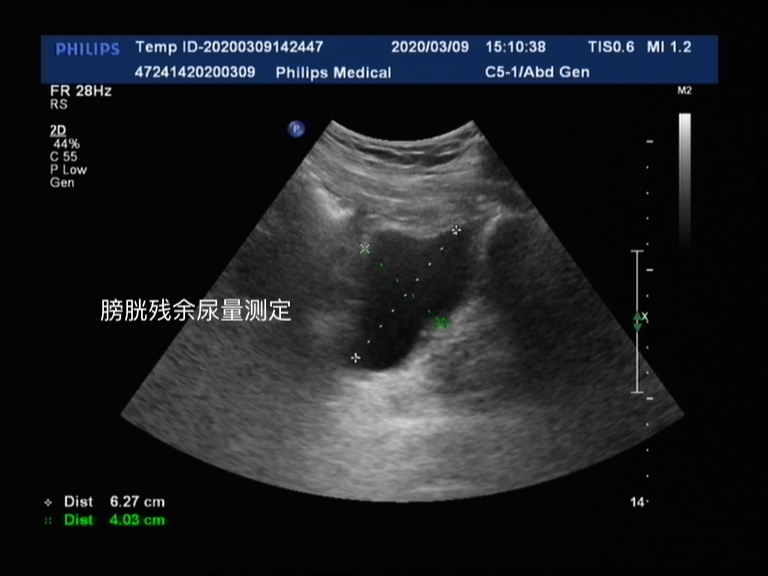

膀胱、残余尿量

膀胱主要是明确患者膀胱内有没有膀胱肿瘤或者血块,同时对于出现排尿障碍的患者,可以明确膀胱储存尿液的能力。结合残余尿量,也就是排尿以后患者膀胱内剩余的小便量,可以大致推测出这个患者排尿的好坏,如图显示,患者就有大量的尿液并没有排出体外。

通过膀胱容量和残余尿量两者结合可以有效分析患者膀胱功能和排尿情况